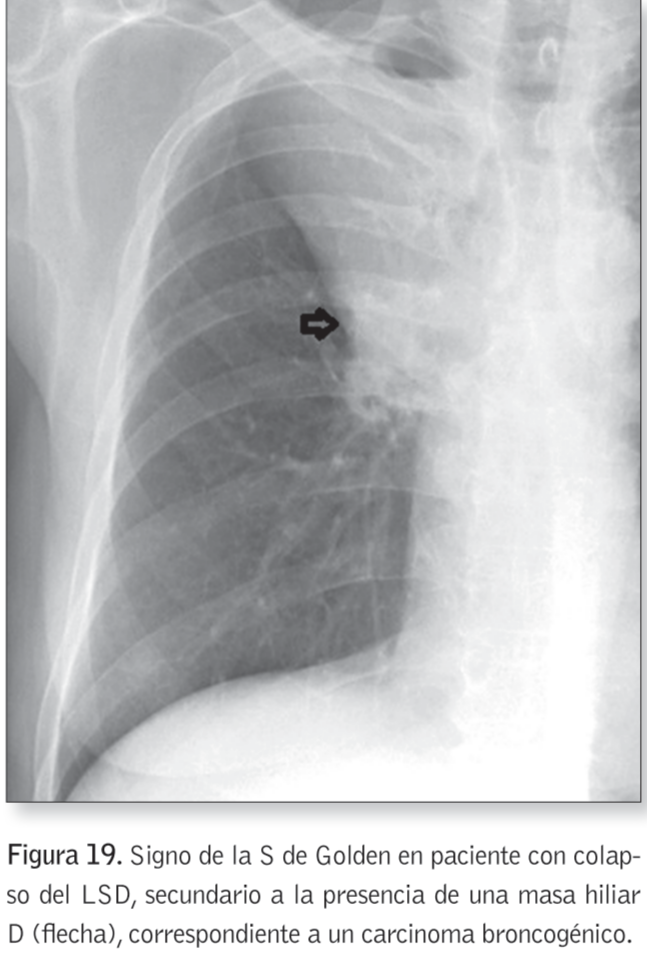

Signo de la S de Golden